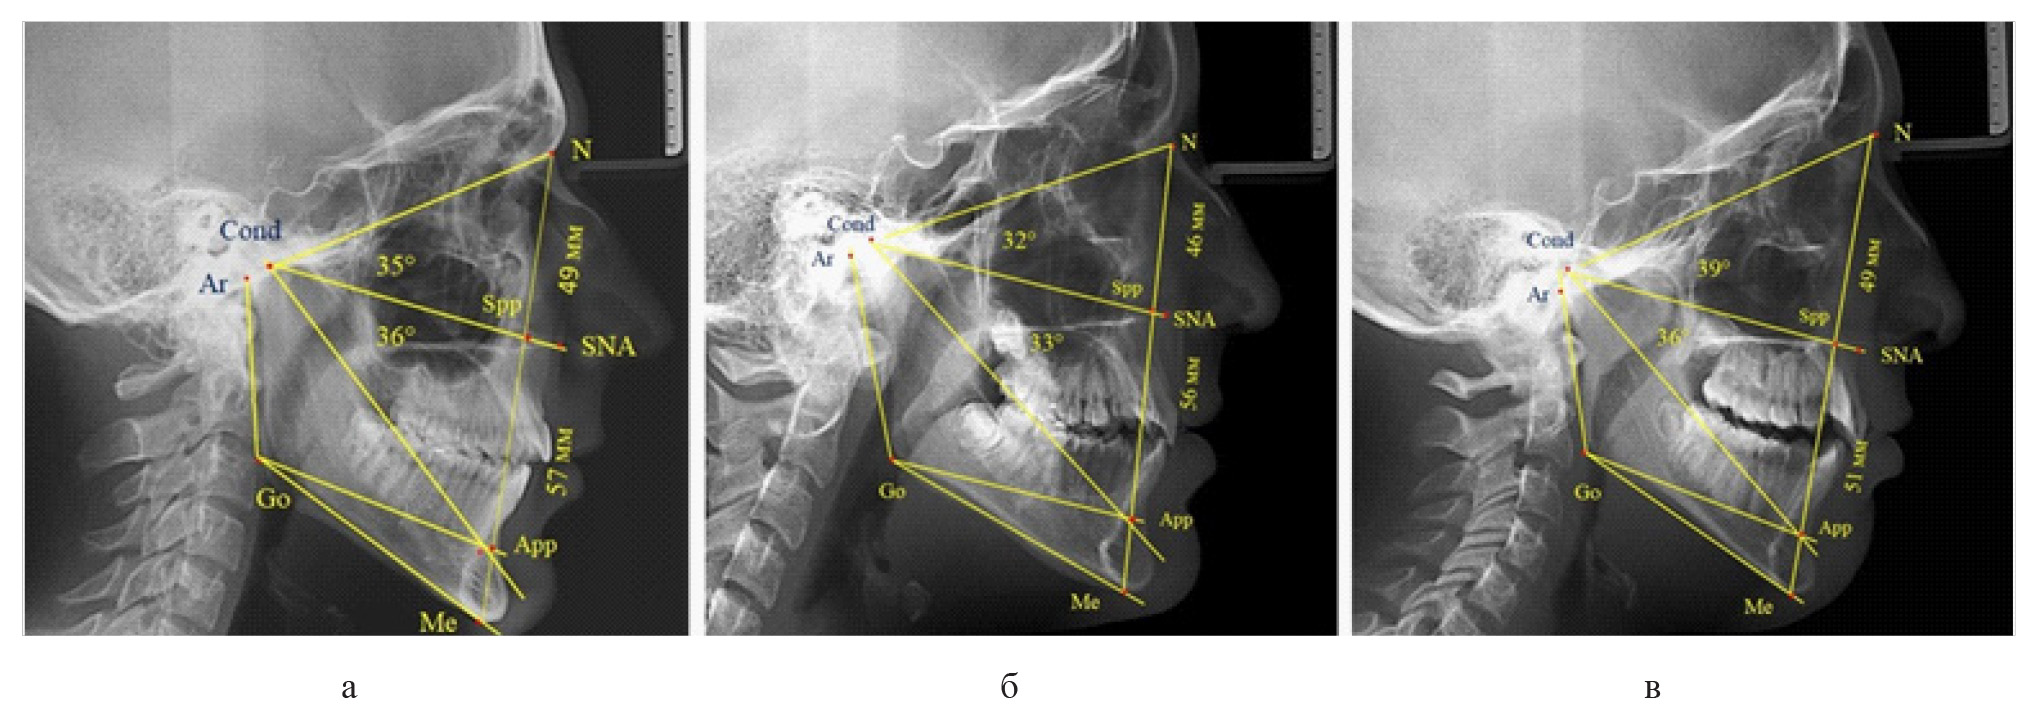

У 6 человек [(10,71 ± 4,13) %], отмечалось увеличение параметров гнатической части до уровня физиологического вертикального показателя, а у 2 человек [(3,57 ± 2,48) %], незначительное снижение гнатической части (рис. 3).

Рис. 3. Сравнительный анализ ТРГ с оптимальными размерами носового отдела и оптимальными (а), укороченными физиологическими (б) и увеличенными физиологическими (в) размерами гнатической части лица